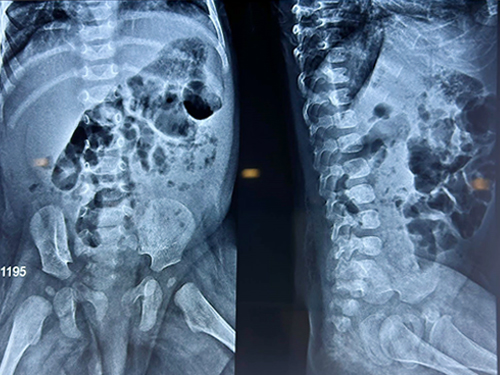

Rectal prolapse in a newborn is very unusual. We have investigated her for any neurological disorder but her lumbosacral spine is perfect.